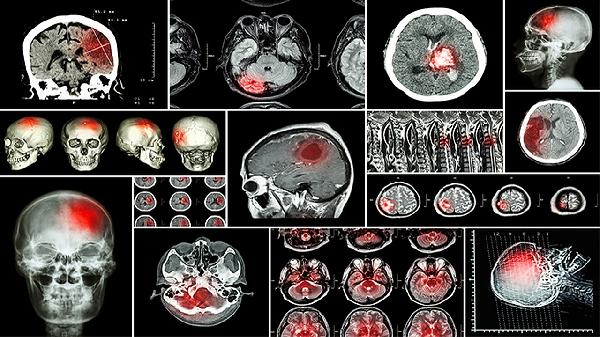

一側腦室寬10毫米不一定是畸形,需結合胎兒發(fā)育情況綜合評估。胎兒側腦室寬度在10毫米以內屬于正常范圍,超過15毫米可能提示腦積水等異常,10-15毫米為臨界值需動態(tài)監(jiān)測。

多數情況下,單純側腦室寬度10毫米可能為生理性變異或暫時性改變。胎兒腦脊液循環(huán)系統(tǒng)發(fā)育過程中可能出現(xiàn)短暫不平衡,導致側腦室輕微增寬。這種情況常在孕晚期自行恢復正常,不會影響胎兒神經系統(tǒng)發(fā)育。超聲檢查未合并其他結構異常時,建議2-4周后復查超聲觀察變化趨勢。孕婦可適當增加富含葉酸的食物如菠菜、動物肝臟,有助于神經管發(fā)育。

少數情況下,側腦室增寬可能伴隨染色體異?;蝻B內結構畸形。如合并透明隔腔消失、小腦發(fā)育異常等征象時,需考慮18三體綜合征、神經管閉合不全等疾病可能。此時建議進行胎兒磁共振檢查評估腦實質發(fā)育情況,同時通過羊水穿刺或無創(chuàng)DNA檢測排除染色體異常。若確診為病理性腦室增寬,需由產科與兒科醫(yī)生共同制定后續(xù)監(jiān)測方案。